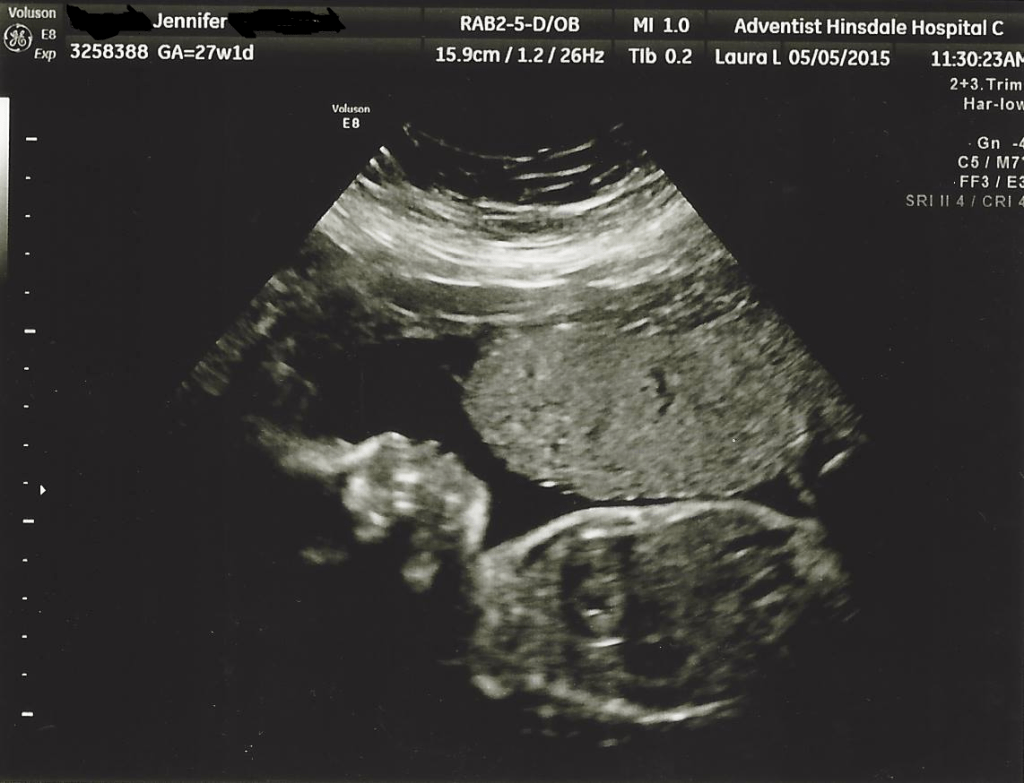

There are different types of TA (1-4). Katja is Type 1. CHD occurs in 1 in 100 infants born every year of those only 1% will have TA. It’s very rare and immediate surgical intervention is needed to repair the heart. We found out at our 20 week pregnancy anatomy scan that Katja had TA. We were extremely fortunate to have the ability to prepare for her arrival. Many TA families don’t learn about a CHD until after birth.